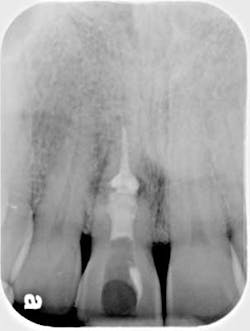

Of all the problems that can occur with implant placement in the anterior, not controlling the zenith of gingival contour may be the most troublesome when it comes to anterior esthetics. Gingival zenith or height of gingival contour is defined as the apex of the gingival height. There are many ways to lose several millimeters of peri-implant mucosa, and it has been shown that even a 1 mm apical displacement of peri-implant mucosa may result in insurmountable limitations in anterior implant esthetics. Things such as deep implant placement, buccal resorption, and relative tooth eruption are just some of the things that can cause this loss of tissue.

When planning surgery with my periodontist, we both decide where we want the zenith to be esthetically, and then plan implant placement 3 mm apical and 2 mm palatal to this location. Biologically speaking, this location will allow us to preserve the zenith from a placement standpoint. Keep in mind that we need to have the tissue healthy and under control prior to starting any procedure.